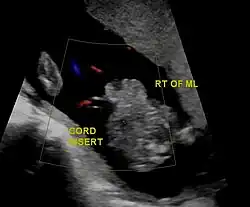

Gastroschisis in ultrasound; defect is to the right of the midline.

During the fourth week of human embryonic development, the lateral body wall folds of the embryo meet at the midline and fuse together to form the anterior body wall.[9] However, in gastroschisis and other anterior body wall defects, this fails to occur due to either one or both of the lateral body wall folds not moving properly to meet with the other and fuse.[10] This incomplete fusion results in a defect that allows abdominal organs to protrude through the abdominal wall, and the intestines typically herniate through the rectus abdominis muscle, lying to the right of the umbilicus. The forces responsible for the movement of the lateral body wall folds are poorly understood, and a better understanding of these forces would help to explain why gastroschisis occurs mostly to the right of the umbilicus, while other ventral body wall defects occur in the midline.[9]